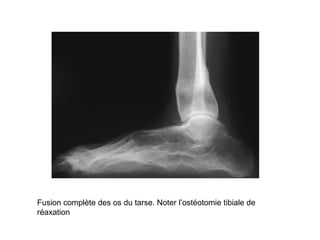

Fusion complète des os du tarse. Noter l’ostéotomie tibiale de

réaxation